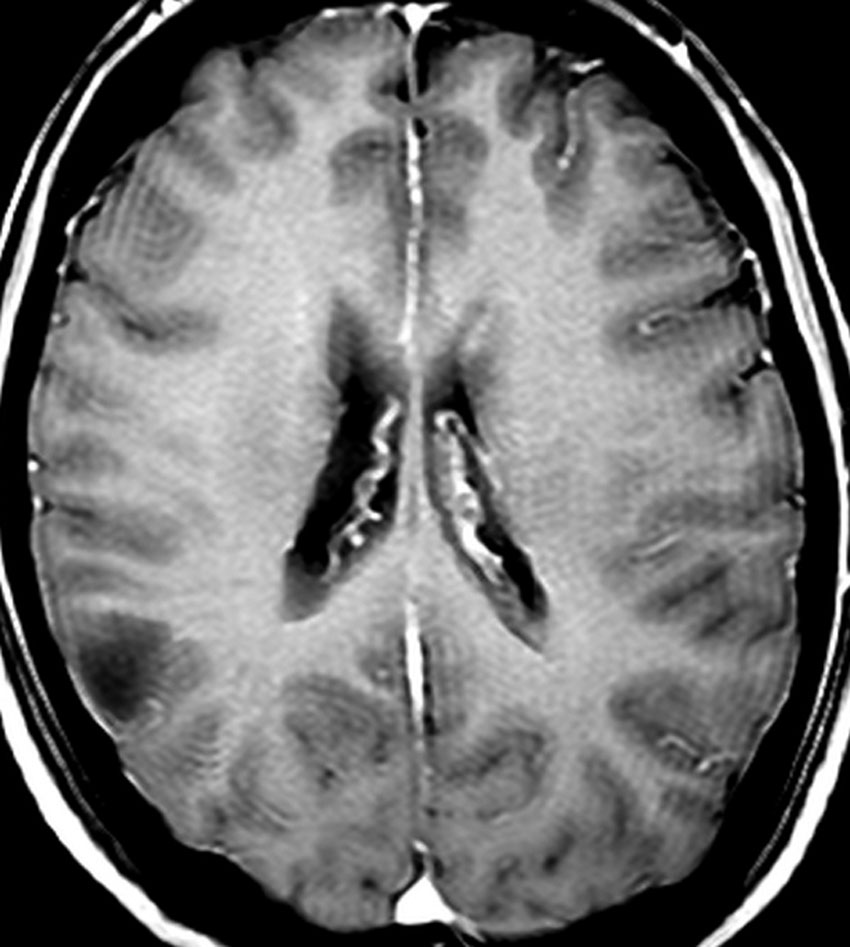

2000年頃の例です。てんかんで発症した20代の女性です。左前頭葉のグリオーマで,手術でほとんどで摘出 subtotal removalして,深部白質に残った病変を経過観察しました。MRIは術後のものです。Ip, 19qはFISHで欠失なし。MIB1は1-2%と低く,MGMTメチレーションなし,diffuse astrocytoma WHO grade 2と組織診断されました。大学病院でしたが当時はIDH遺伝子診断はしておらず,びまん性星細腫グレード2でした。これもまた当時の標準的な考えで,進行があるまでは経過観察としました。

2年後に急激な進行 rapid progressionしました。ガドリニウム増強所見も出現しました。IMRTで59.4Gy/27分割の放射線治療とテモゾロマイド化学療法をしましたが,腫瘍は抑制できませんでした。

放射線治療後も進行して,白質に沿った浸潤伸展をしました。脳幹部橋の右側まで浸潤 invasionしています。この伸展は星細胞系腫瘍の特徴でもあります。

2016年分類では,diffuse astrocytoma WHO grade 2です。しかしこれはおそらく,2021年分類では IDH wild-type astrocytoma grade 4とされます。